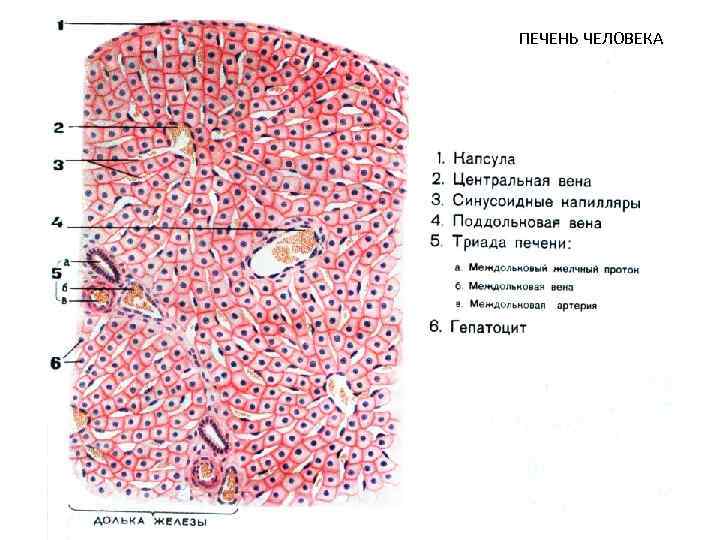

ПЕЧЕНЬ ЧЕЛОВЕКА

CV- центральная вена BD- желчные протоки * - синусоидные капилляры

1 - внутридольковый синусоидный капилляр, 2 - эндотеиальная клетка, 3 - поры в эндотелии, 4 - звездчатый макрофаг, 5 - перисинусоидальное пространство Диссе, 6 - ретикулярные волокна, 7 - микроворсинки гепатоцитов, 8 - гепатоциты, 9 - желчный капилляр, 10 - перисинусоидальный липоциты (клетки Ито), 11 - жировые включения, 12 - эритроциты

Желчный капилляр Плотный контакт Десмосома Звездчатый макрофаг (Купферовская клетка) Эндотелиоцит Перисинусоидальное пространство Диссе Ретикулярное волокно Липоцит Ямочная клетка Плотный контакт Ретикулярное волокно

Синусоидный капилляр печени 1 -эндотелий с порами, 2 - пространство Диссе

Желчный капилляр печени 1 - ядро, 2 -митохондрия, 3 - лизосома с желчными пигментами, 4 - желчный капилляр

Желчный капилляр

1 - зона оптимального кровоснабжения, 2 - зона умеренного кровоснабжения, 3 - зона наихудшего кровоснабжения (наиболее уязвима при интоксикациях)

Препарат № 139 «Печень человека»

Препарат № 139 «Печень человека»

Препарат № 139 «Печень человека»

Центральная вена и синусоидные капилляры